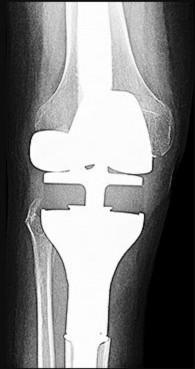

During a posterior-stabilized total knee arthroplasty, the surgeon assesses the flexion and extension gaps.

The extension gap is symmetric and perfectly balanced, but the flexion gap is excessively tight. Which of the following is the most appropriate surgical adjustment?

Explanation

When the extension gap is balanced but the flexion gap is tight, the goal is to increase the flexion gap without altering the extension gap. This can be achieved by decreasing the anteroposterior (AP) size of the femoral component, translating the femoral component anteriorly, or recessing the PCL (if retaining it, though this is a PS knee so PCL is already gone). Resecting more proximal tibia affects both gaps. Downsizing the AP femur size uniquely increases the flexion gap.